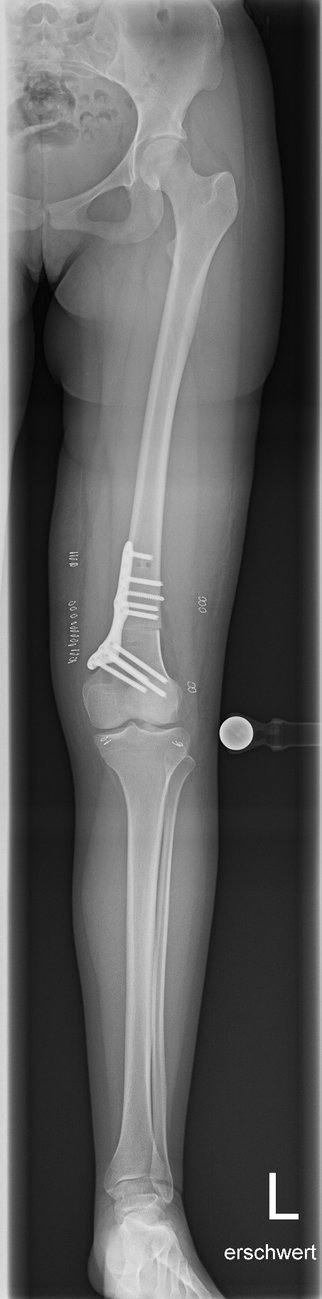

Tibiakopf Fraktur

Die arthroskopisch assistierte Frakturversorgung (insbesondere am Tibiakopf) im Rahmen von Band- bzw. Kombinationsverletzungen ist ebenfalls ein Schwerpunkt der Abteilung. Der ärztliche Direktor PD Dr. med. Schlumberger ist im DKG-Komitee „Frakturen“ vertreten.